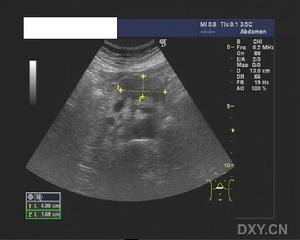

2、B超檢查 B超檢查是診斷胰假性囊腫的一項簡便而有效的手段,典型者於上腹可探及一位置明確、範圍肯定的液性暗區。B超對鑑別包塊和囊腫特別有助,對胰假性囊腫的診斷正確率可達73%~91%。動態的超聲探查可了解囊腫大小的改變。此外,在B超引導下,可作囊穿刺,抽取囊液作生化和細胞學檢查。